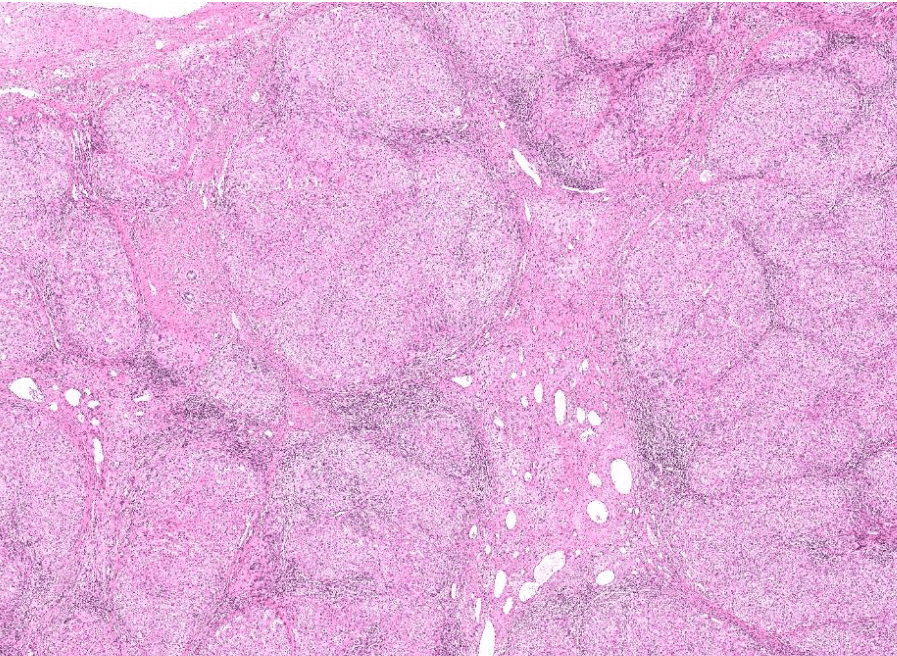

colon cancer